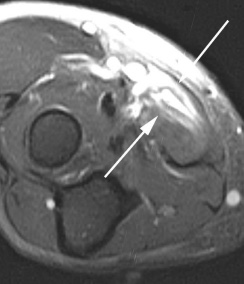

(Справа) На осевой MPT PDBИ FS у этого же пациента определяется перелом, окруженный отеком костного мозга с высоким сигналом. Повреждение этой области локтевого отростка у спортсменов-метателей, применяющих верхний бросок, не является редкостью и поэтому ею следует учитывать при дифференциальной диагностике боли в локтевом суставе у этих пациентов.

На МРТ локтевого сустава при любом переломе видна реакция костного мозга. Это помогает в диагностике, если перелом сразу не виден на рентгенограмме. В дальнейшем можно прицельно дообследовать подозрительную область. При консолидировавшихся переломах на МРТ остается видна линия перелома, а окружающий костный мозг нередко подвергается жировой дегенерации. МРТ в СПб стало необходимым компонентом обследования пациентов с травмой суставов и осуществимо в высоких полях или открытом МРТ. МРТ СПб дает возможность исследовать методом МРТ локтевой сустав в разных центрах, однако, наш опыт позволяет рекомендовать обследование именно у нас.

МРТ локтевого сустава. Т2-взвешенная МРТ, аксиальный срез ниже суставной щели. Разрыв двуглавой мышцы плеча (стрелка).

МРТ локтевого сустава. Т2-взвешенная аксиальная МРТ. Разрыв круглого пронатора (стрелка).